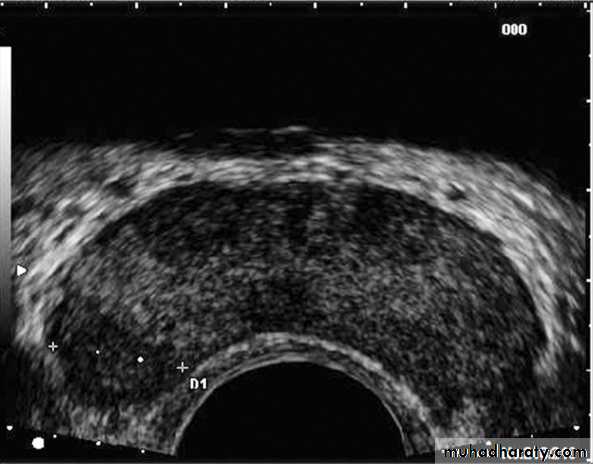

TRUS & biopsy (sixtant biopsy).